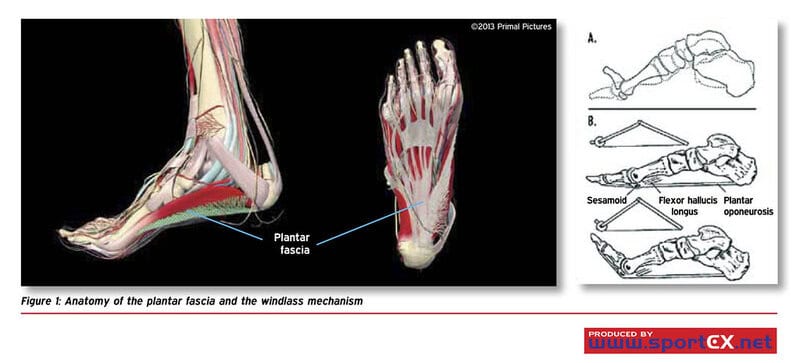

A detailed diagram shows the plantar fascia stretching along the foot arch, highlighting inflammation typical of plantar fasciitis. | Image source: flickr.com

The plantar fascia is a thick band of tissue running along the bottom of the foot, supporting the arch and absorbing shock with every step.

While it’s crucial for bipedal movement, its design is far from perfect.

Many people develop painful inflammation known as plantar fasciitis, especially after prolonged standing or running.

This common foot ailment reveals how our evolution toward upright walking still comes with structural compromises. Source